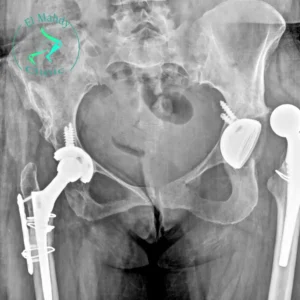

يعد مفصل الورك الصناعي من الحلول الطبية المتقدمة التي أحدثت تغييرًا جذريًا في حياة الملايين من المرضى حول العالم. فهو يوفر حلًا فعالًا؛ للتخفيف من

يعد مفصل الورك الصناعي حلًا فعالًا للمرضى الذين يعانون من مشكلات شديدة في مفصل الورك، حيث يساعد في استعادة الحركة وتخفيف الألم. ولكن، يعد من